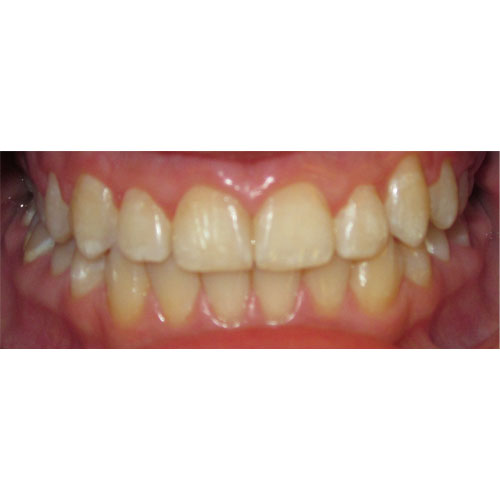

Nasze rezultaty